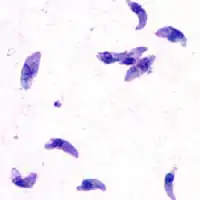

T. gondii tachyzoites

Acute toxoplasmosis is often asymptomatic in healthy adults.[13][14] However, symptoms may manifest and are often influenza-like: swollen lymph nodes, headaches, fever, and fatigue,[15] or muscle aches and pains that last for a month or more. It is rare for a human with a fully functioning immune system to develop severe symptoms following infection. People with weakened immune systems are likely to experience headache, confusion, poor coordination, seizures, lung problems that may resemble tuberculosis or Pneumocystis jiroveci pneumonia (a common opportunistic infection that occurs in people with AIDS), or blurred vision caused by severe inflammation of the retina (ocular toxoplasmosis).[15] Young children and immunocompromised people, such as those with HIV/AIDS, those taking certain types of chemotherapy, or those who have recently received an organ transplant, may develop severe toxoplasmosis. This can cause damage to the brain (encephalitis) or the eyes (necrotizing retinochoroiditis).[16] Infants infected via placental transmission may be born with either of these problems, or with nasal malformations, although these complications are rare in newborns. The toxoplasmic trophozoites causing acute toxoplasmosis are referred to as tachyzoites, and are typically found in bodily fluids.[17][18]

While rare, skin lesions may occur in the acquired form of the disease, including roseola and erythema multiforme-like eruptions, prurigo-like nodules, urticaria, and maculopapular lesions. Newborns may have punctate macules, ecchymoses, or "blueberry muffin" lesions. Diagnosis of cutaneous toxoplasmosis is based on the tachyzoite form of T. gondii being found in the epidermis.[31] It is found in all levels of the epidermis, is about 6 by 2 μm and bow-shaped, with the nucleus being one-third of its size. It can be identified by electron microscopy or by Giemsa staining tissue where the cytoplasm shows blue, the nucleus red.[32]

In its lifecycle, T. gondii adopts several forms.[33] Tachyzoites are responsible for acute infection; they divide rapidly and spread through the tissues of the body. Tachyzoites are also known as "tachyzoic merozoites", a descriptive term that conveys more precisely the parasitological nature of this stage.[34] After proliferating, tachyzoites convert into bradyzoites, which are inside latent intracellular tissue cysts that form mainly in the muscles and brain. The formation of cysts is in part triggered by the pressure of the host immune system.[35] The bradyzoites (also called "bradyzoic merozoites") are not responsive to antibiotics. Bradyzoites, once formed, can remain in the tissues for the lifespan of the host. In a healthy host, if some bradyzoites convert back into active tachyzoites, the immune system will quickly destroy them. However, in immunocompromised individuals, or in fetuses, which lack a developed immune system, the tachyzoites can run rampant and cause significant neurological damage.[33]